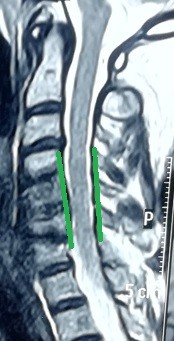

multiple cervical herniated discs